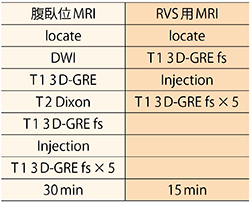

RVS用MRIは,脂肪抑制併用3D-GREシーケンス(日立:TIGRE)を用いる。造影剤自動注入器を用い,呼吸停止下で撮像を行う。RVS用MRIは,腹臥位MRIとは別日に撮像している。当院での腹臥位乳房MRIとRVS用MRIの撮像法を表1に示す。

表1 当院における腹臥位乳房MRIとRVS用MRIの撮像法